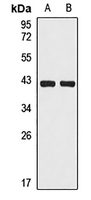

Western blot analysis of HLA-B expression in HepG2 (A), A549 (B) whole cell lysates. (Predicted band size: 40 kD; Observed band size: 40 kD)

Western blot analysis of HLA-B expression in HepG2 (A), A549 (B) whole cell lysates. (Predicted band size: 40 kD; Observed band size: 40 kD) -